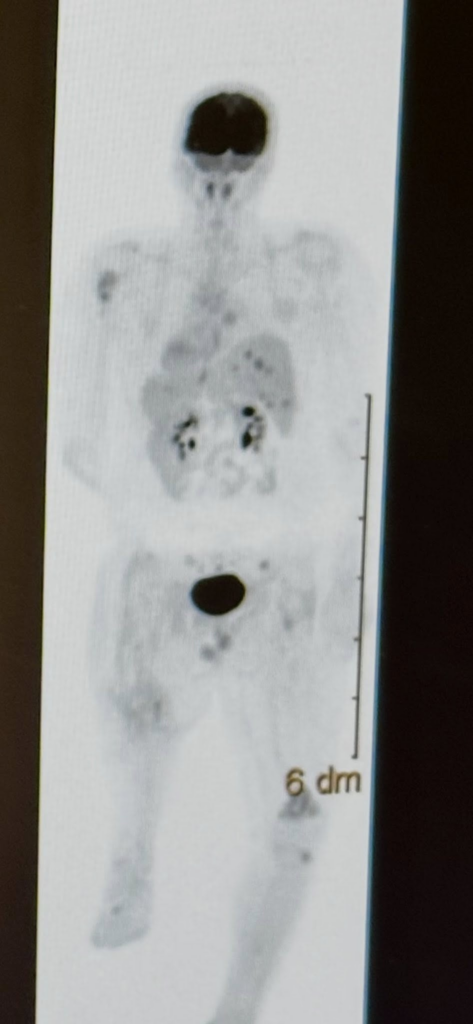

But when the illuminated medical scans appeared on the viewing board at exactly 3:29 PM, hope froze in place.

Doctors studied the scans carefully, exchanging looks that required no words. The “miracle treatment,” the one that had inspired cautious optimism among the medical team, had not produced the results they had hoped for. The disease had not retreated. In some areas, it had advanced.

Will’s courage didn’t erase the reality of his illness. It didn’t make the scans disappear. But it changed the emotional gravity of the situation.